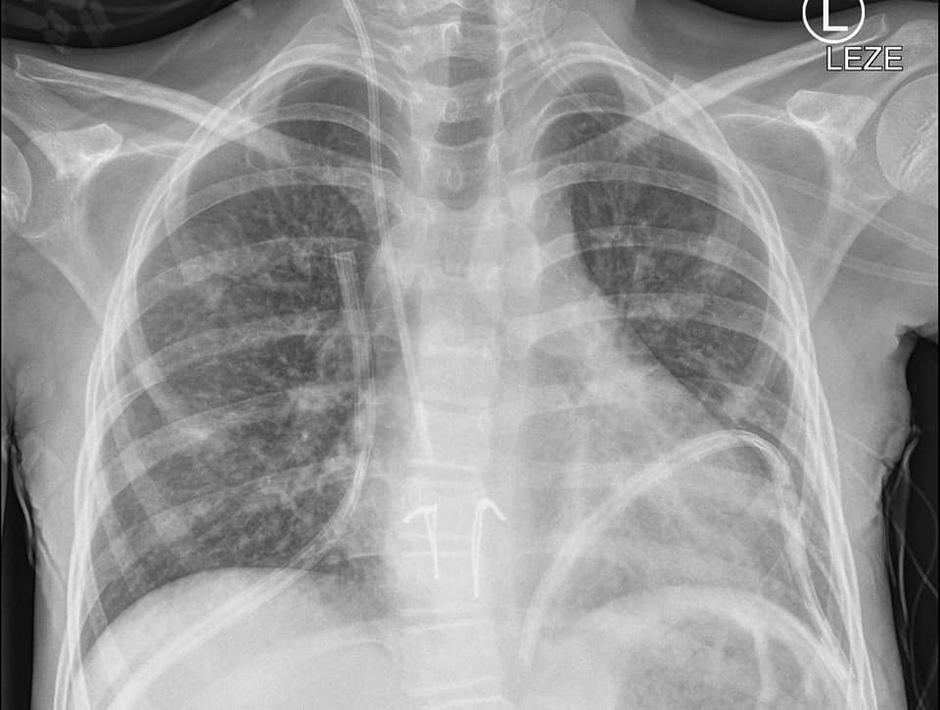

14. letno deklico s cistično fibrozo so operirali v noči na soboto in to je bila prva presaditev pljuč pri otroku pri nas. Deklica pa je že drugi dan po posegu samostojno zadihala z novimi pljuči in se sedaj odlično počuti.

Po besedah predstojnika, se je s presaditvijo že kar mudilo, stanje se je deklici poslabševalo, zato so transplantacijo morali opraviti v kakšnih treh mesecih ali morda pol leta. Najprej je bilo sicer predvideno, da bi jo operirali na Dunaju, a so tam kljub prošnjam sporočili, da nimajo zmogljivosti in presaditve ne morejo opraviti. "Imeli smo srečo, da so v hitrem času dobili pljuča primerno velikega otroka," je dodal. Pljuča so pripeljali s falconom iz tujine, v spremstvu treh kirurgov. Kot je pojasnil zdravnik, so takšni prevozi stresni, saj se lahko marsikaj zgodi na poti.